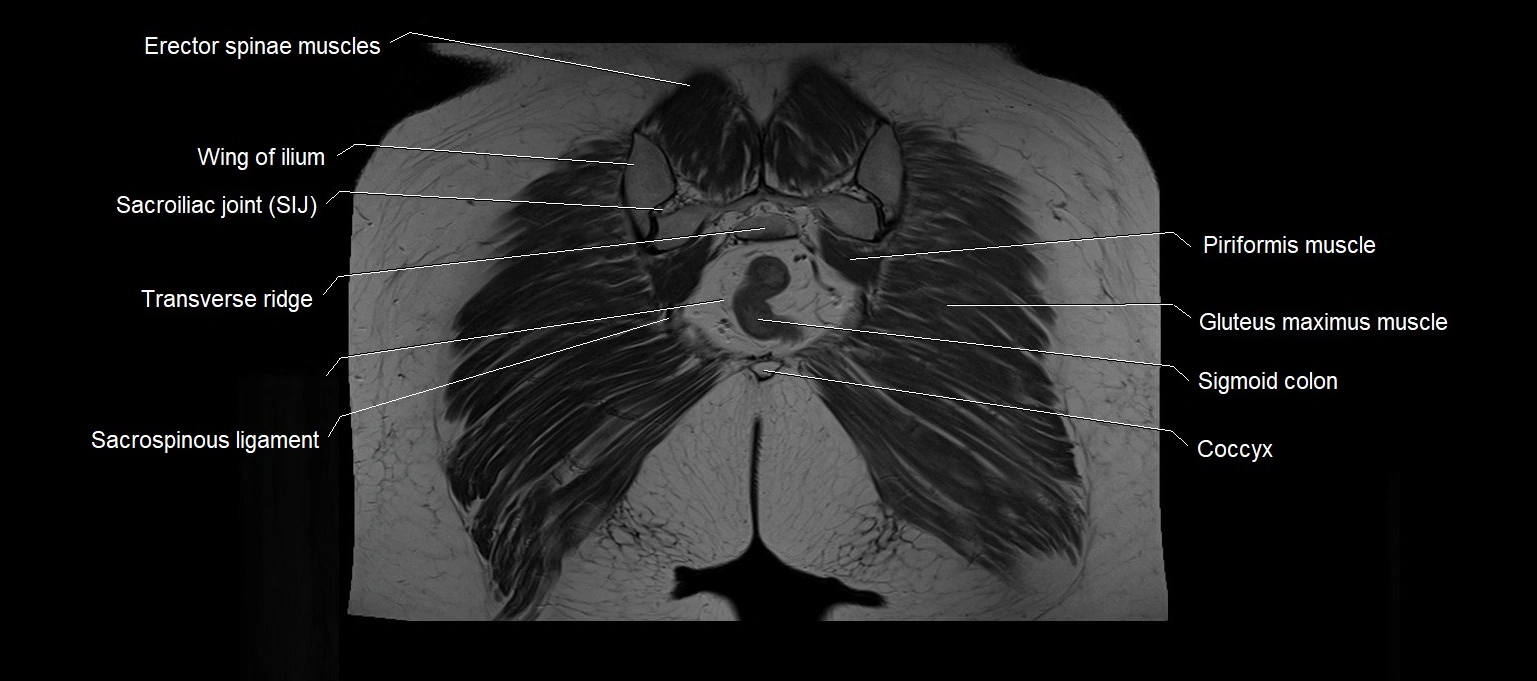

- Coccyx

- Erector spinae muscles

- Piriformis muscle

- Sacrospinous ligament

- Sacrum

- Sigmoid colon

- Sacroiliac joint